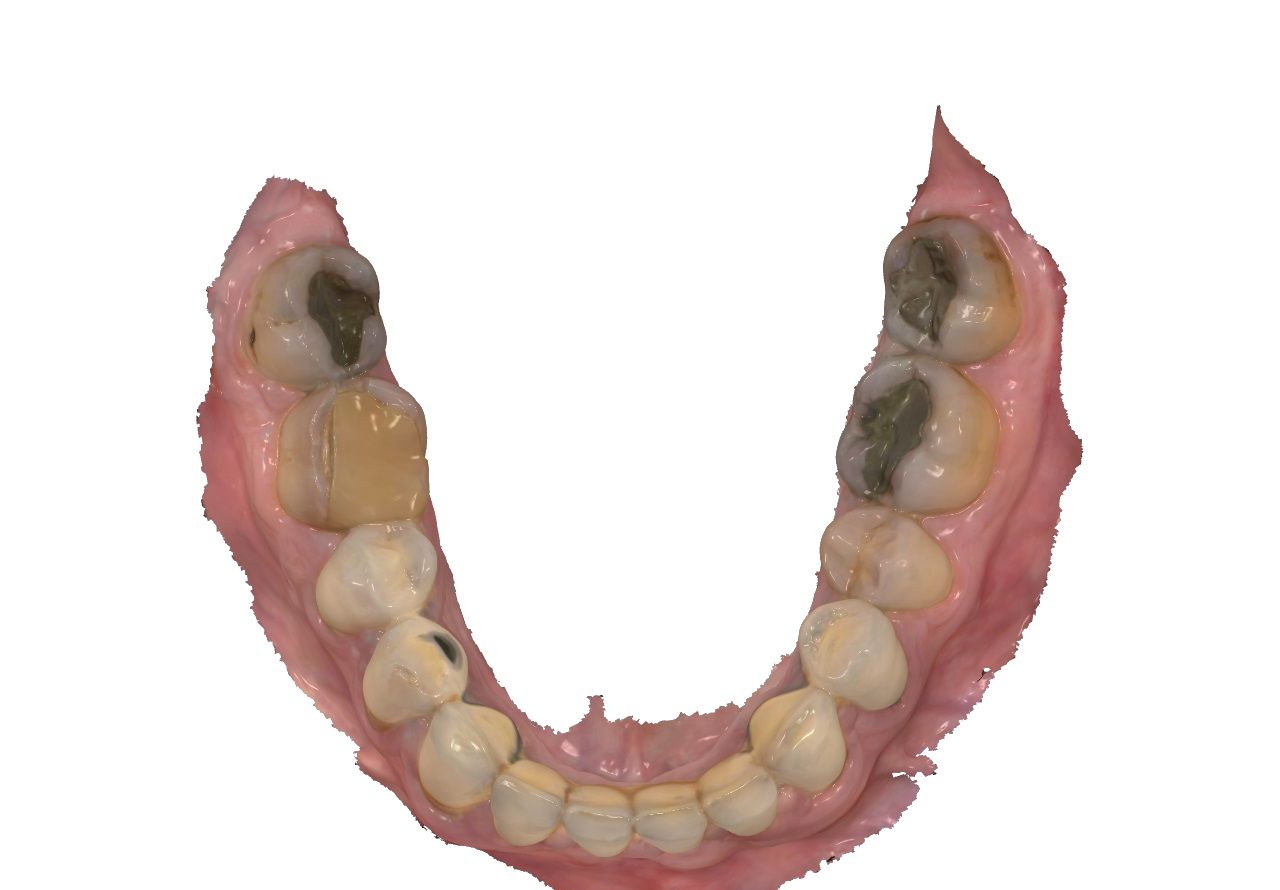

Unterkiefer

48 f f 38

47 F2 c c F2 37

46 KM ww c F2 36

45 KM kw 35

44 KM kw kw KM 34

43 KM kw kw KM 33

42 SKM b b SKM 32

41 BM b b BM 31

• dent. Aufbau: 9x Zahn 12-21, 33, 34, 43-46

• Füllungstherapie Zähne: 16, 26, 27, 36, 37, 47